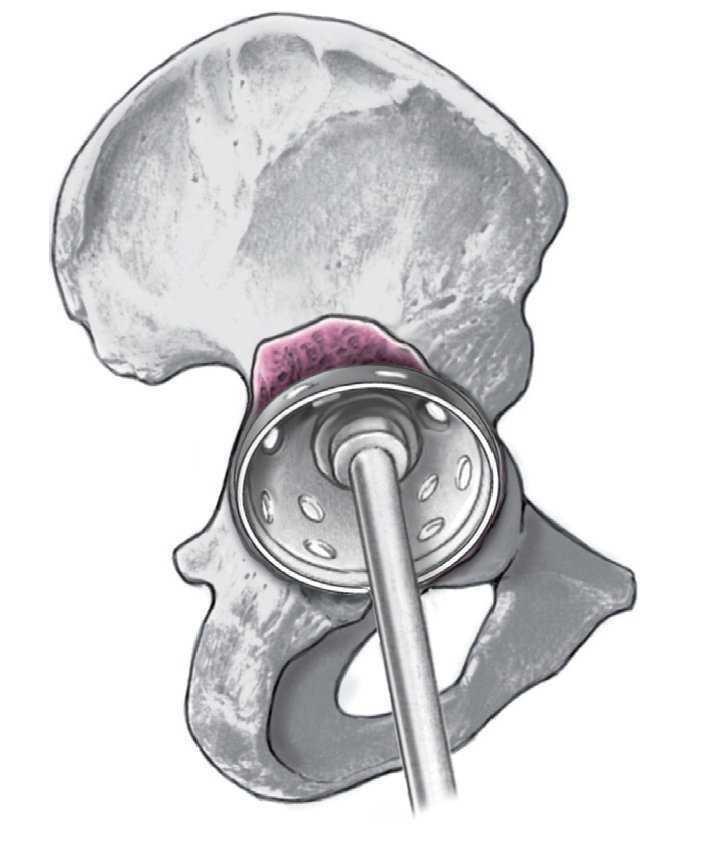

Figura 10. Colocación del hueso fresado en el suelo acetabular y ocasionalmente en el defecto acetabular preexistente (lo último a menudo no es necesario). Introducción de un componente acetabular de pared fina de una talla superior a la de la última fresa, con lo cual se obtiene en las superficies de contacto un pressfit de 4 mm.

Figura 11. Introducción del cierre central polar del componente AllofitSTM.